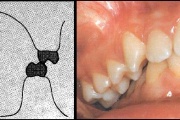

Esimese jäävmolaari ektoopiline lõikumine

Ravijärgne seis. Jäävhammas on täielikult lõikunud.

) Röntgenülesvõte. Ülemise esimese jäävmolaari lõikumine on takistatud 2. piimamolaari tõttu